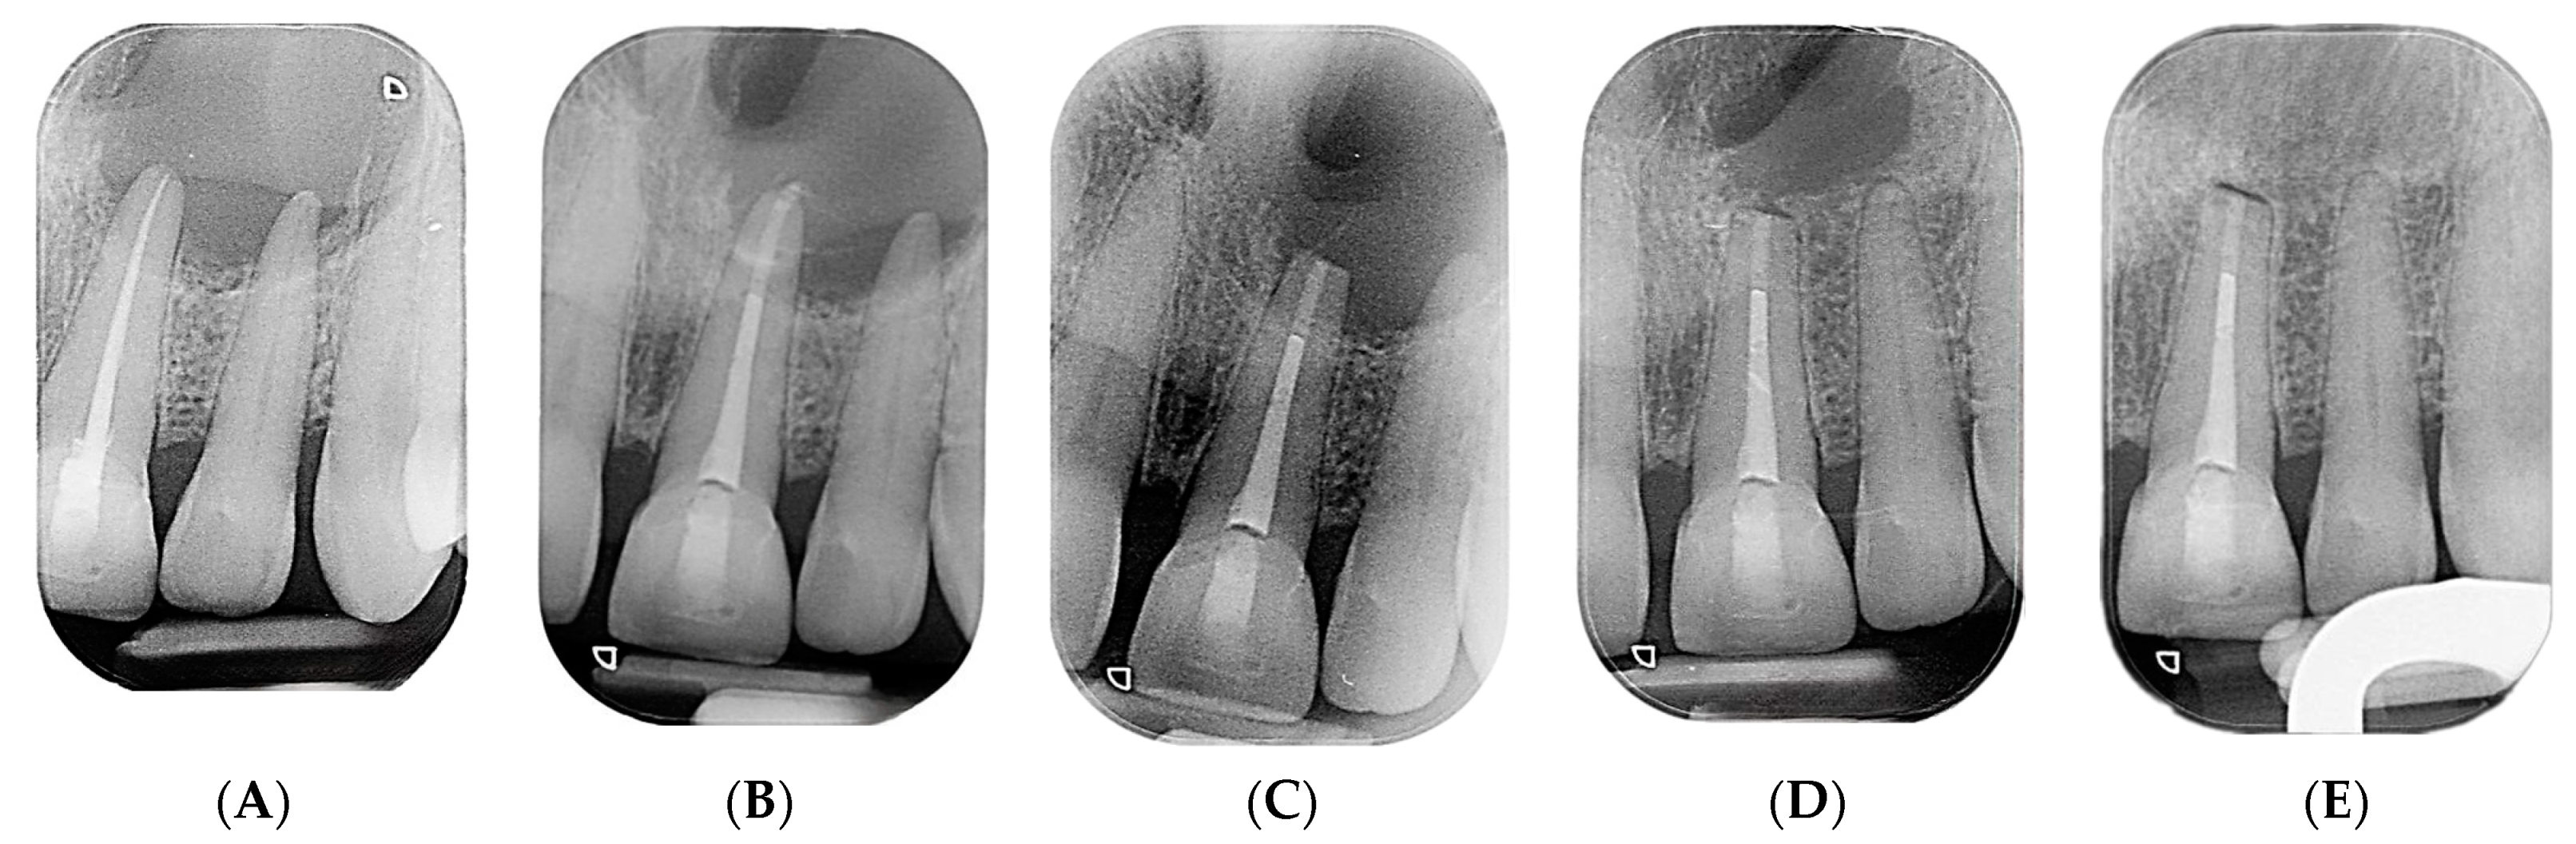

2. Case Presentation

2.2. Delivery of Treatment

2.4. Healing of the Defect and Follow Up